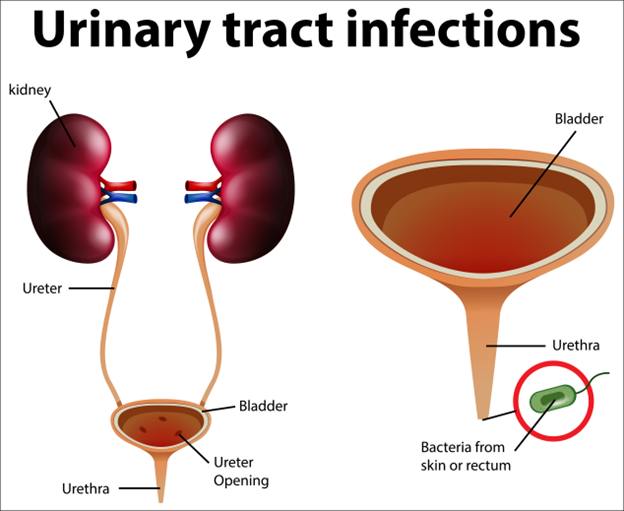

Recurrent UTIs: When It Could be a Chronic UTI

Urinary tract infections (UTIs) are a common health problem, affecting millions of people every year. While most UTIs are acute

A Closer Look at Chronic Urinary Tract Infection (UTI)

A chronic or persistent urinary tract infection is an ongoing infection of the urinary tract for a prolonged period despite

Acute Pyelonephritis: Recognizing the Warning Signs

Acute pyelonephritis is a potentially severe infection of the kidneys that requires immediate medical attention. This condition occurs when bacteria,

Know About Acute pyelonephritis

A type of urinary tract infection (UTI) that affects the kidneys. It occurs when bacteria enter the urinary tract, travel